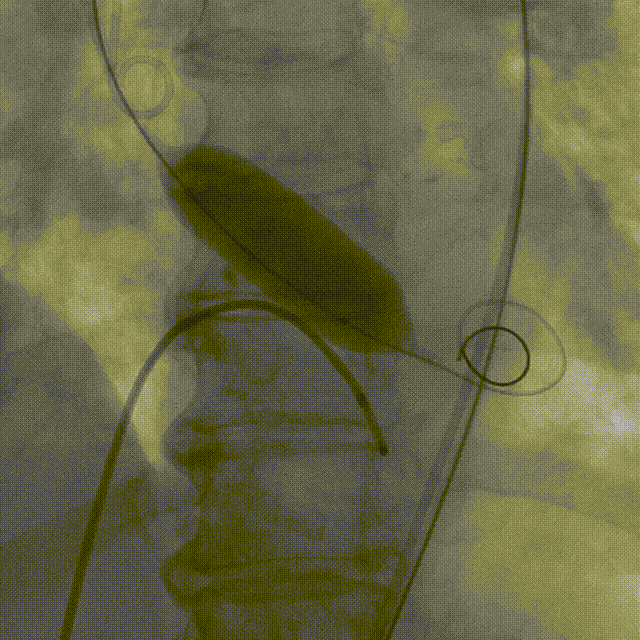

TaurusNXT植入过程

术中影像

主动脉根部造影

TaurusAtlas 18mm球囊预扩张

瓣膜释放至工作位造影

最终造影